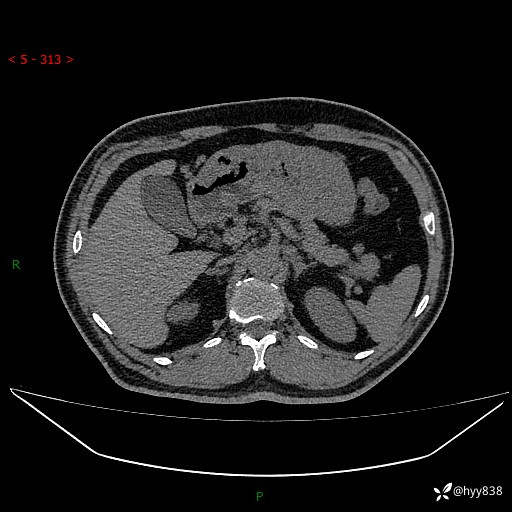

胰腺CT平扫